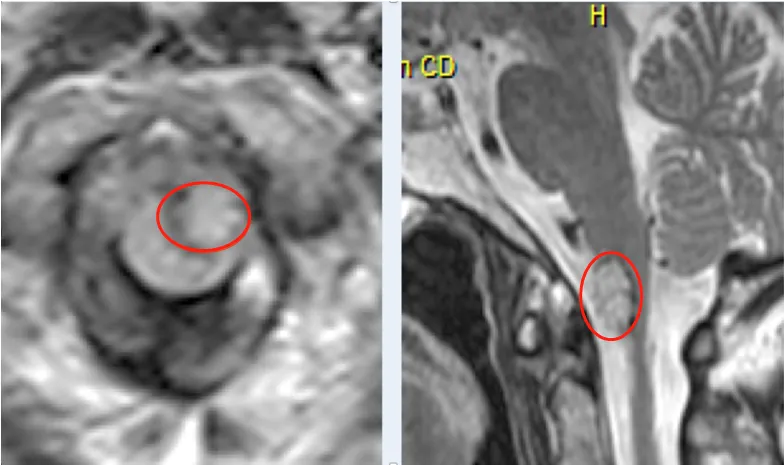

脑干这块地方,对咱们脑子太重要了。要是这儿出问题,轻的可能脖子以下动不了,重的连自己喘气都费劲,甚至会要命。 这地方还特别小,做手术难度大得很。病变跟颈髓、神经、血管贴得...